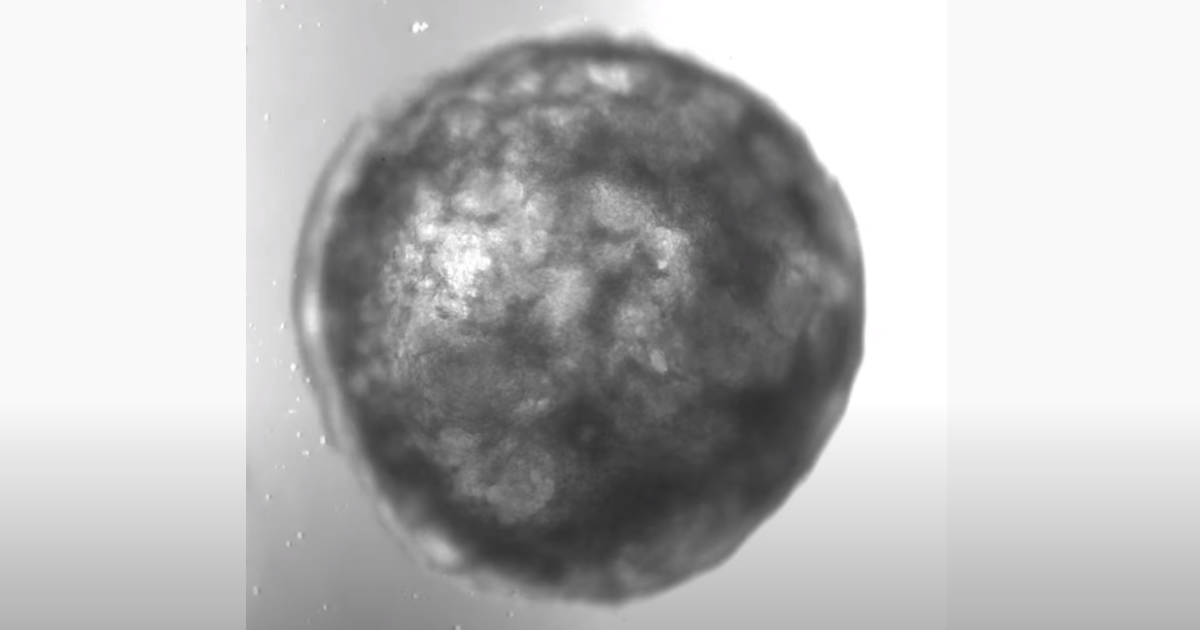

Австрійські вчені успішно виростили маленьке штучне серце. Це перший подібний мініатюрний орган з однією камерою, що самоорганізується.

Як повідомляє ТСН, фахівці впливали на людські стовбурові клітини, використовуючи шість сигнальних шляхів, які відповідають за розвиток серця у людського ембріона, внаслідок чого модель сформувалася самостійно.

Такий зовнішній вплив призводить до поділу стовбурових клітин, дозволяючи штучному органу рости і формувати нові шари під контролем учених.

Команда вважає, що завдяки органоїду можна буде тестувати серцеві препарати на безпеку та ефективність, перш ніж відправляти на клінічні випробування.

Це допоможе без шкоди для здоров’я людей визначити, чи є ліки токсичними і наскільки вони дають раду з завданням. Тепер учені сподіваються виростити серце з декількома камерами, ще більше схоже на орган людини.